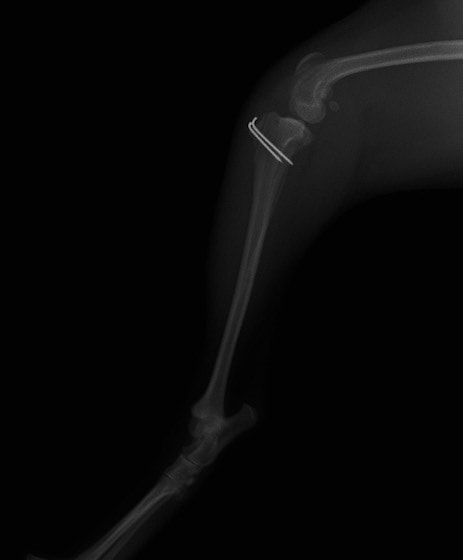

■ 症例24 キャバリア 7か月

左右膝蓋骨内方脱臼(左:グレードⅣ 右:グレードⅢ)

以前から左右後肢の跛行が認められ、整形外科学的検査・レントゲン検査により左右の膝蓋骨脱臼が認められた。症状が重度である左膝の膝蓋骨脱臼整復術を行った。外科手技は縫工筋及び内側広筋の解放、脛骨粗面の外側転位、滑車ブロック形造溝術、内外側関節方の縫縮を実施した。術後一か月時点で、左の膝蓋骨は安定しており経過は良好である。

本症例は成長期における重度の膝蓋骨脱臼であり、術後の再発の可能性もあるため、経過をしっかりと観察していく必要がある。また、今回手術を実施していない右膝に関しても経過を観察し、手術を検討していくこととする。